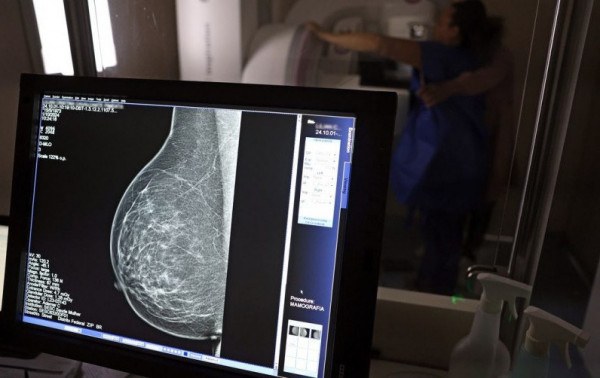

Outubro Rosa: mulheres têm exames gratuitos na rodoviária de Brasília | Foto: Agência Brasil

No mesmo local, a dona de casa Lilian Cristina Cavalcanti, fez pela primeira vez uma mamografia, a radiografia específica das duas mamas que possibilita a identificação precoce de alterações nos seios. Com 51 anos e mãe de três filhos, ela admite que, até hoje, deixou a questão de lado por falta de tempo e por achar que seria difícil conseguir a vaga em uma unidade pública de saúde. "Nunca tentei. Não tenho paciência para ficar na fila esperando e, como nunca senti nada [no autoexame da mama], deixei passar", confessou.

Mas, chegou a hora dela realizar a mamografia bilateral. Lilian Cristina se posicionou em pé, em frente ao aparelho e, imóvel, teve as mamas comprimidas em diferentes ângulos para captura das imagens detalhadas. No fim, ela saiu da carreta do Sesc com impressões positivas sobre o exame. "Achei que doía mais, mas foi bem tranquilo. Agora, espero ansiosa pelo resultado do exame."

André Abreu, do Sesc-DF, explica que as imagens em alta resolução captadas pelos mamógrafos são enviadas automaticamente aos profissionais do Hospital de Barretos (SP) para análise e emissão do laudo médico, em até 30 dias. "Se o laudador já identificar visualmente um câncer, ele avisará a equipe de Brasília que poderá ter que repetir o exame e esta deverá encaminhar a mulher examinada como paciente ao Hospital de Base de Brasília". Nos demais casos, quando for constatada a normalidade das mamas, a mulher receberá o laudo em um envelope nominal no prazo citado, no mesmo local - a rodoviária do Plano Piloto.